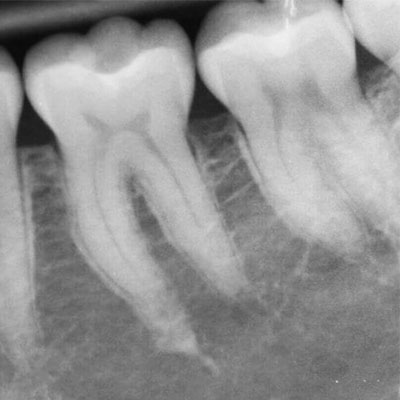

O exame radiográfico periapical proporciona ao dentista a visualização do dente em toda sua extensão, desde a coroa ao ápice, o espaço periodontal e o tecido ósseo.

A radiografia periapical ou RX periapical é um exame utilizado para mostrar radiograficamente a anatomia de um ou mais dentes (desde a coroa ao final da raiz), assim como as estruturas anatômicas vizinhas, ou seja, que estão ao redor dos dentes.

Esta radiografia pode ser usada para estudar qualquer dente (molar, pré-molar, e incisive os caninos) seja na arcada dentária superior ou na inferior para fins de diagnóstico e tratamento.